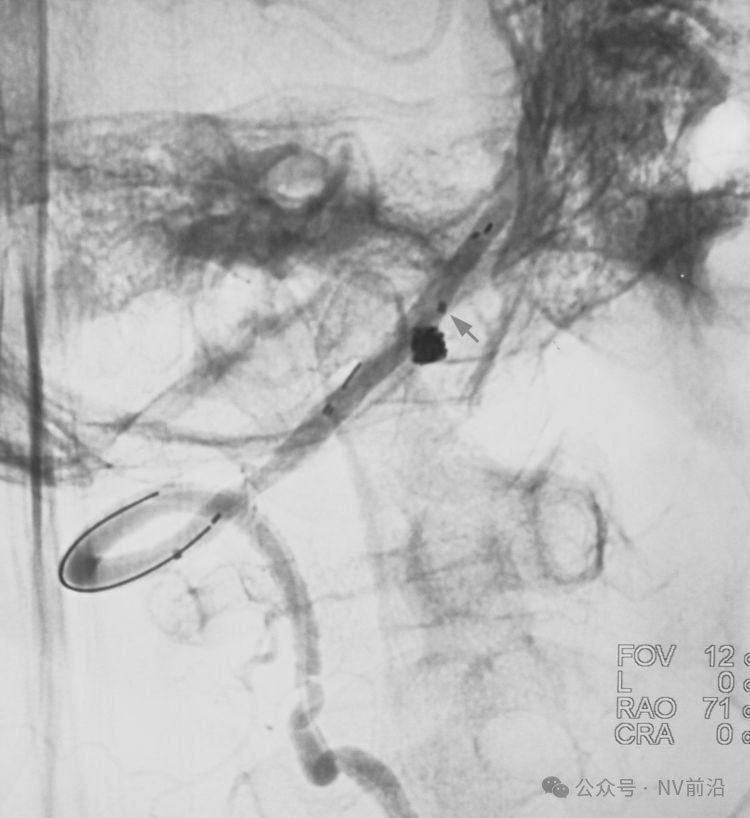

跨瘤颈释放Solitaire 4×20支架(蓝线),压住微导管(红线),在支架保护下经返折的微导管送入弹簧圈填塞瘤腔。

依次送入QC-2-4-3D,2-3-Helix,1.5-2-Helix,1.5-2-Helix四枚弹簧圈,最后一枚弹簧圈将管头(箭头)顶出瘤腔。